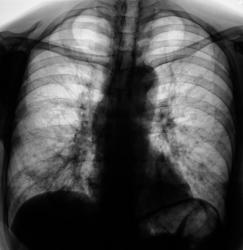

При расшифровке цифровых флюорограмм пациентка была "взята на контроль".

Произведено стандартное дообследование.

Жалоб пациент не предъявляет. Возникло сильное желание без промедлений направить пациентку на консультацию в ОКБ. Коллегиально решили провести противовоспалительную терапию, а затем "провести контроль".

После проведения противовоспалительной терапии проведен "контроль".

Ваше мнение уважаемые коллеги?

А млжет быть эти крупные очаги - метастазы?

По всей видимости, придется направить на консультацию к онкологам.